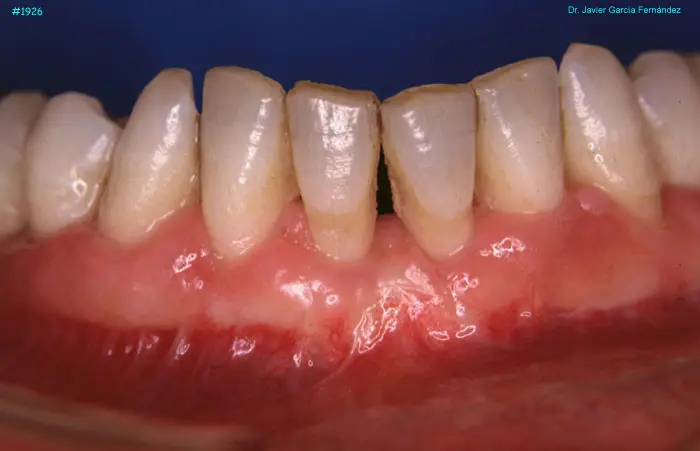

image 73